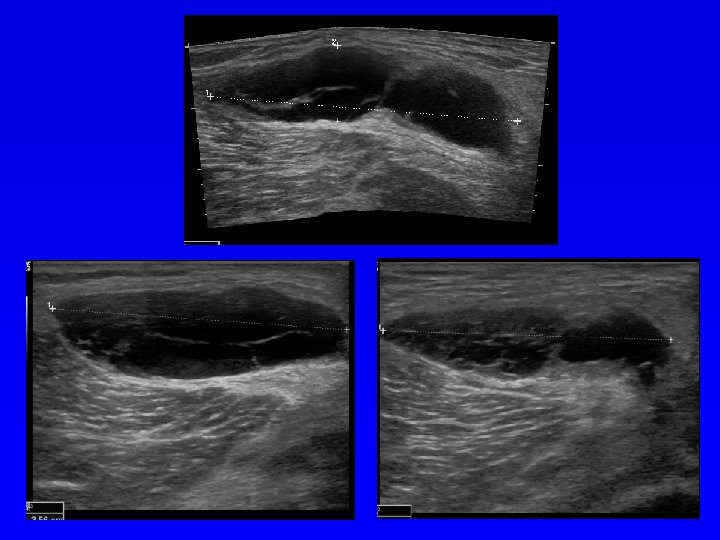

Ultrasonografie Podle echogenity (odrazivosti) lze uspořádat tkáně: Kost (výrazně echogenní), vazivo, sval, tuk, chrupavka, tekutina (minimální echogenita). Anechogenní struktura- černá Hypoechogenní struktura- šedá Hyperechogenní - bílá Diagnostika měkkých tkání Diagnostika nádorů Diagnostika VDK Zjištění výpotku v kloubu Další využití